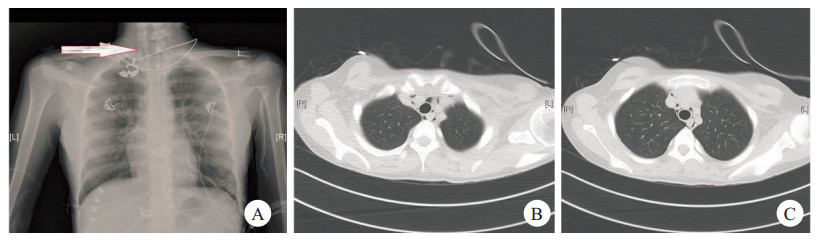

1 资料与方法 1.1 一般资料患者女性,18岁,主因“腹部不适10 d,呕吐5 d”来诊。既往体健,否认糖尿病史。入院查体:体温36.0℃,脉搏72次/min,呼吸18次/min,血压101/60 mmHg。双肺呼吸音清,未闻及干湿啰音,无胸膜摩擦音。心律齐,各瓣膜区未闻及杂音,无心包摩擦音。腹软,无压痛、反跳痛、肌紧张。双下肢无水肿。辅助检查:血糖29.8 mmol/L,尿糖4+,尿酮体4+。血气分析示:酸碱度7.15,二氧化碳分压15.0(mmHg),氧分压116.0(mmHg);血常规:白细胞14.51×109/L, 红细胞5.98×1012/L,血红蛋白183.0 g/L,红细胞压积0.5,血小板374.0×109/L;血肝功、肾功、电解质均正常;患者入院后仍有间断呕吐,诉有胸痛,立即予以胸片检查,胸片(图 1A):双肺纹理增多,纵隔气肿待排;查胸部CT(图B, C):颈部、纵隔积气。

| 图 一 颈部可见低密度影(箭头处) |